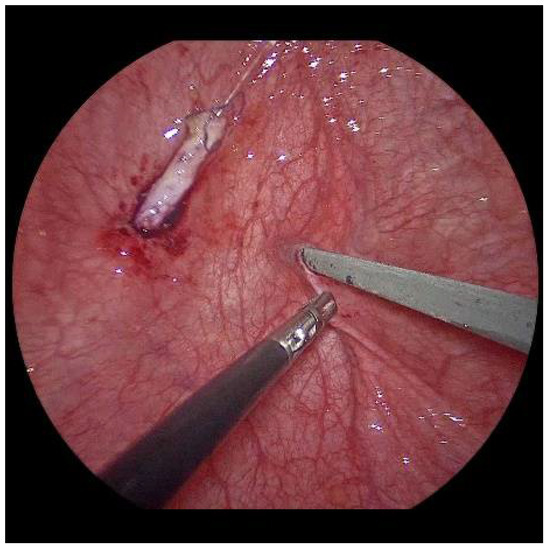

Now, the ureter is intubated with a 3 or 4 Fr. silicone tube, followed by subtle circumferential electrical mucosa incision with a fine dissecting needle (Figure 3). The ureteral release is continued using an electrical hook for at least 4 to 6 cm until it can be positioned without tension to the opposite ostium (Figure 4). Duplicate ureters are intubated twice and mobilized together. If bilateral, the submucosal tunnel is created between the two ostial incisions. If not, an additional mucosal incision is made 1 cm canially of the opposite regular ostium (Figure 5).

Figure 4. After mobilization, the left ureter can be shifted to the right ostium with little tension.